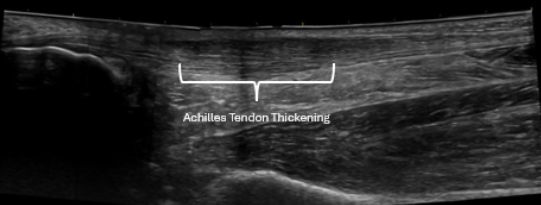

Diagnostic ultrasound is especially useful for common injuries seen in active adults and athletes, including:

• Achilles & ankle injuries

• Chronic tendinopathy